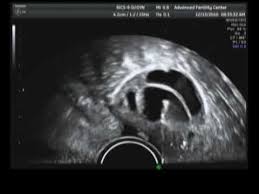

After Iui Process Video : 5 minutes success after iui.. After about a week following the procedure, your doctor may want to check your progesterone levels and your uterine lining with an ultrasound. So, how does the iui method to get pregnant work? Pay your surgery/medical expense cost at 0% emi? Often doctors tell women to expect implantation to occur around 5 days after the iui procedure. Though there has been no evidence of swimming interfering in the iui process, still, it is a good idea to avoid swimming for 48 hours, after the iui procedure.

The whole process doesn't take very long. In short, it is a simple process that can be performed at the doctor's office. Get medical payment card by letsmd!for inquiry click here : After about a week following the procedure, your doctor may want to check your progesterone levels and your uterine lining with an ultrasound. Performing the iui the day before or day after will lower the chance for iui success.

After about a week following the procedure, your doctor may want to check your progesterone levels and your uterine lining with an ultrasound.